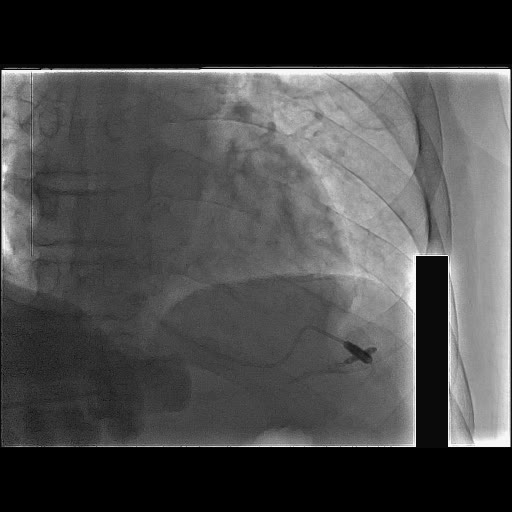

暂时缓解了心脏压塞,但迂曲的血管,是下一个难关!导丝、球囊根本不能到位,在延伸导管的帮助下完成球囊扩张及支架植入。

支架植入也是非常困难,最后经过深插GC,延伸导管尽量靠前支撑下,完成了支架植入。开通后可以发现RCA非常大,范围很广。